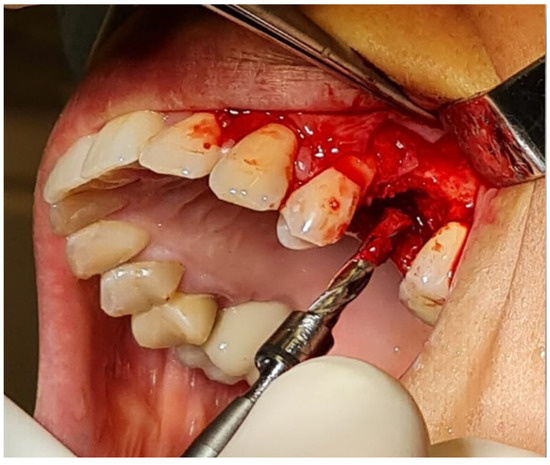

2.4. Surgical Procedure (In Vivo)

2.5. Bone Biopsies (In Vivo)